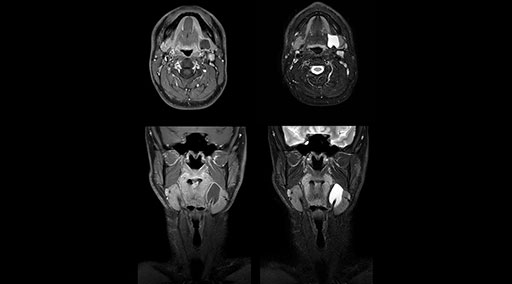

“Without using an endorectal coil we do our prostate MR at 0.5 mm resolution, following the European society of urology protocol [1]. For certain joints we use a virtual arthroscopy protocol with 1 mm pixel size and 2 mm slice thickness. Ingenia really excels in our neurography, brachial plexus and prostate scans. Our neurologists insist on using our 3.0T for those,” Dr. Kaakaji adds.

“Our DMG Lisle location includes a cancer center, so soft tissue neck scans, brachial plexus scans, and prostate scans are common. For these exams, mDIXON TSE provides excellent images with and without fat suppression all while helping us reduce repeats and work more efficiently,” Mr. Duffy says.

“mDIXON TSE raises our diagnostic confidence with its homogeneous

fat suppression. Neck exams and rheumatology patients are two examples where mDIXON TSE is especially useful,” Dr. Kaakaji says. “For us it’s also an efficiency boost in exams where we need pre and post T1-weighted images with great fat suppression.”